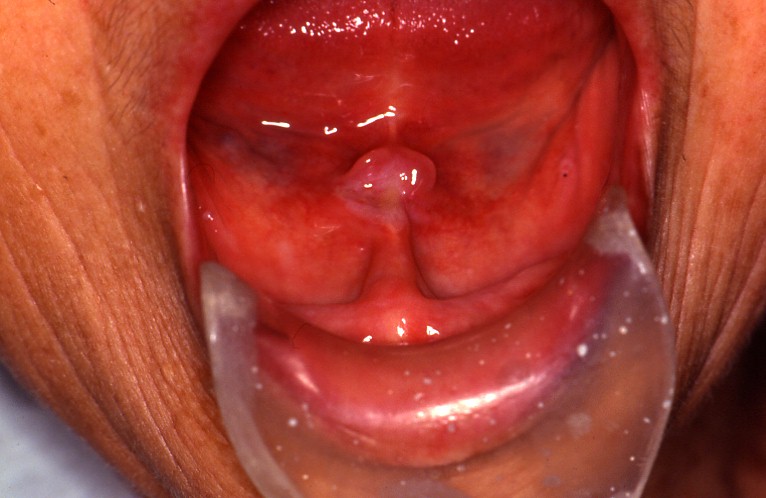

症例1:総入れ歯による褥瘡性潰瘍。義歯調整で治癒します。

症例2:むし歯の鋭縁による舌の褥瘡性潰瘍。糖尿病の方で、なかなか治りませんでした。

症例3:上の総入れ歯による褥瘡性潰瘍。入れ歯の辺縁に一致して潰瘍があります。

潰瘍は孤在性で有痛性、通常は軽度です。

不正形で限局的な陥凹として認められ、辺縁周囲は発赤帯が接してみられ、潰瘍底面は平坦で赤色、または肉芽組織表面の壊死により黄白色を呈します。

腫瘍性病変のような隆起性ではなく、結核性潰瘍のように穿堀性もありません。

褥瘡性潰瘍の好発部位としては、舌(舌縁、舌尖、舌小帯)、頬粘膜、歯肉と頬(舌)との移行部、口蓋があげられます。